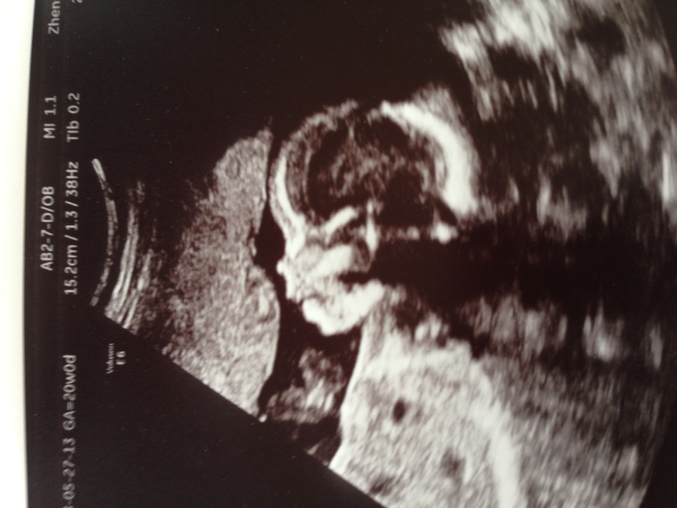

marusia в Благополучная беременность 13 лет Наша долгожданная доченька))) Пол малыша Сегодня были на УЗИ))) нам сказали что все хорошо и у нас доченька))) Мы счастливы)))она милашка))) Посмотрите еще 20 записей на эту тему Отменить Ответить Лина интересно,фотки мальчиков на этом сроке по комплекции что ли отличаются от принцесс??? 17.06.2013 Ответить Босиком_по_росе М-м-м...какая она у вас милая! 27.05.2013 Ответить marusia Спасибо)))))))Вам тоже СЧАСТЬЯ))) 28.05.2013 Ответить Екатерина Чудесная девочка, уже на узи видно красавицу)) 27.05.2013 Ответить marusia Спасибо за приятные слова)) Удачи)) 28.05.2013 Ответить Елена Даже на фото УЗИ видно, какая красавица будет! Лапуля! 27.05.2013 Ответить marusia Спасибо)))) Очень приятно)) 27.05.2013 Ответить Елена Поздравляю! Девочка - это здорово))) Фотка с УЗИ классная, четкая такая))) 27.05.2013 Ответить marusia Спасибоооооооо)))))Вам легких родов)))))) 27.05.2013 Ответить Елена И вам спасибо!)) 27.05.2013 Ответить Marinechi Класс!! Поздравляю с ожиданием принцесски! 27.05.2013 Ответить marusia Спасибо))) 27.05.2013 Ответить Катеринка очаровательна поздравляю с дочкой ! 27.05.2013 Ответить marusia Спасибо))) А Вам сказали уже кто? 27.05.2013 Ответить Катеринка В 16 недель увидели лапочку-дочку ! Это если ничего не отрастет к 21 неделе ))) 27.05.2013 Ответить Ксю 27.05.2013 Ответить marusia Спасибо))) 27.05.2013 Ответить Юлия Поздравляю 27.05.2013 Ответить Виктория Поздравляю Вас)))) это прекрасное милое создание))) 27.05.2013 Ответить marusia Спасибо)) Я верю что у всех нас ББешечек все будет хорошо)) 27.05.2013 Ответить Ну кто же там живет? не пойму! Второе узи и узист экстрасенс ? :) Чаты Беременных Выберите чат: Январята-2026 Февралята-2026 Мартята-2026 Апрелята-2026 Майчата-2026 Июнята-2026 Июлята-2026 Августята-2026